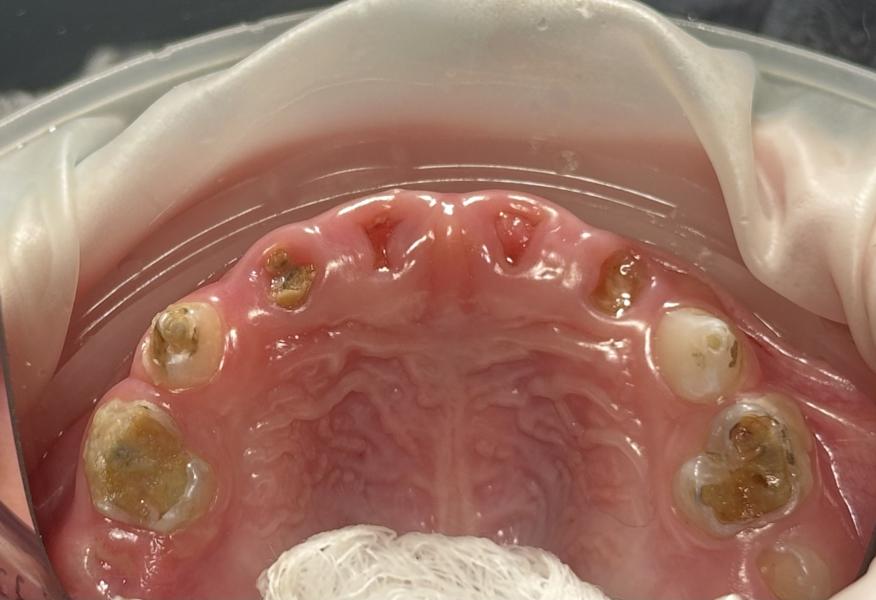

Мамочки, к Вам вопрос! Почему такая печальная ситуация может случиться с зубками детей? Какие Ваши предположения?

Да, генетика - это тоже намаловажный фактор, оказывающий влияние на состояние зубов ребенка. Но все же гигиена, режим/рацион питания, а также внутренние дефициты ребенка также играют решающую роль

Ночное кормление из бутылки, кто-то из родственников может с ложки 🥄 кормил пережевывая за ребенка, питание.

Упустил момент когда только появился налёт .

Браво, это одна из очень значимых и популярных причин, но к сожалению многие родители по незнанию пренебрегают этим фактором(